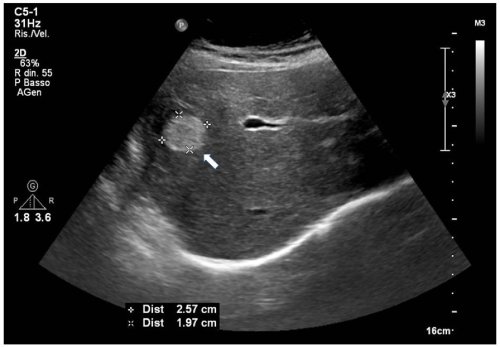

- Siêu âm: thường là khối tăng âm tương đối đồng nhất, bờ rõ (có thể thay đổi ở u không điển hình).

Hình 3. Hình ảnh u máu gan trái trên chụp cắt lớp vi tính